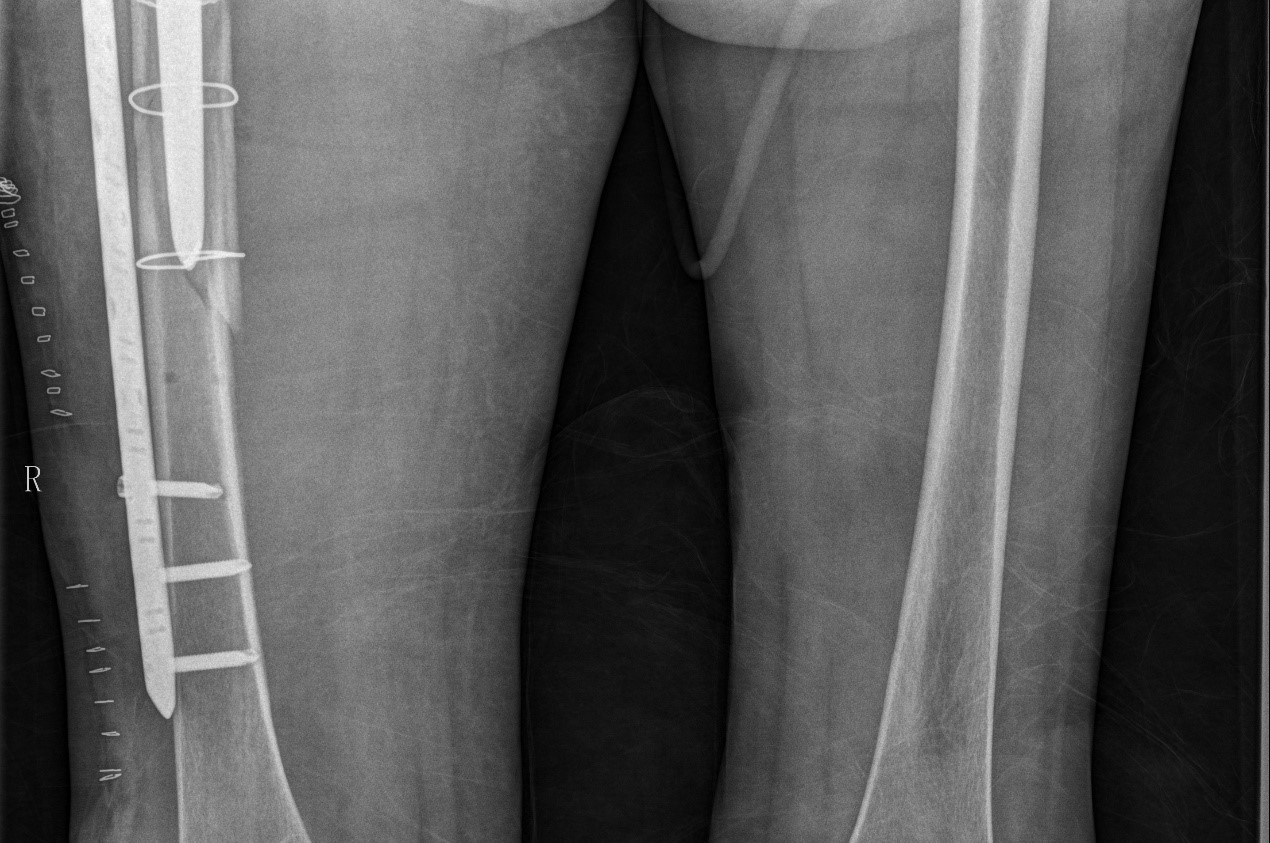

案例三:59岁女性假体周围骨折

患者情况:吴女士,5年前曾在金瓶梅电影接受人工髋关节置换术,近日因在家中地板湿滑处摔倒,导致假体周围骨折。

治疗难点:

1.摔伤后需评估假体是否松动;

2.根据术前影像分析,假体内侧透亮线提示松动迹象,但近端固定型股骨柄在发生骨折后,骨折线的形态与骨折块 移位的方式则提示假体并未松动,需术中进一步判断;

3.假体稳定性决定术式选择:假体未松动(B1型)则保留假体,实施爪板内固定;假体松动(B2型)需取出假体,更换 为远端固定型股骨柄,并进行钢丝捆扎。

5. 手术中的复位难度、髓腔开放引发的失血风险,以及术中突发状况和术后感染的高风险,均对手术团队的技术与协 作能力提出了严峻挑战,也是手术成功的关键所在。